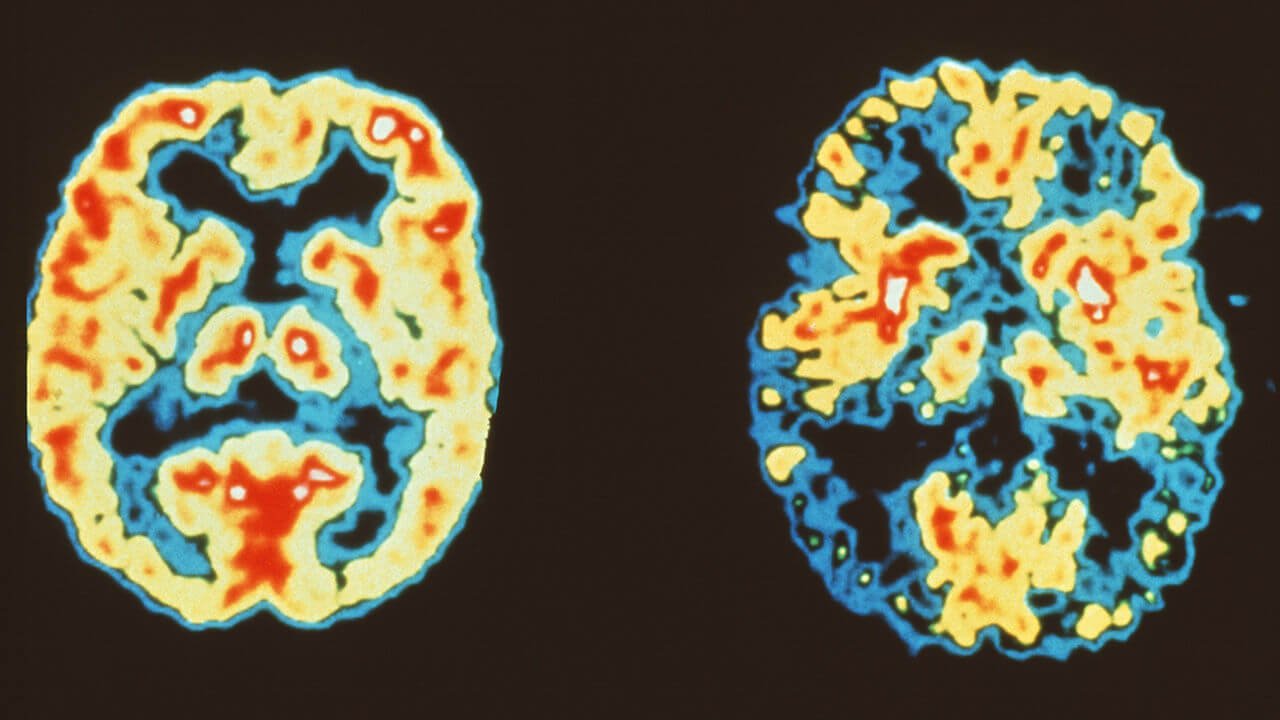

Repetitive negative thoughts associated with Alzheimer's disease

the brain Scan of a healthy person (left) and scan of brain of person with Alzheimer's (right) Despite the fact that in everyday life we rarely talk about Alzheimer's every year with her face at least 10 million people. According ...